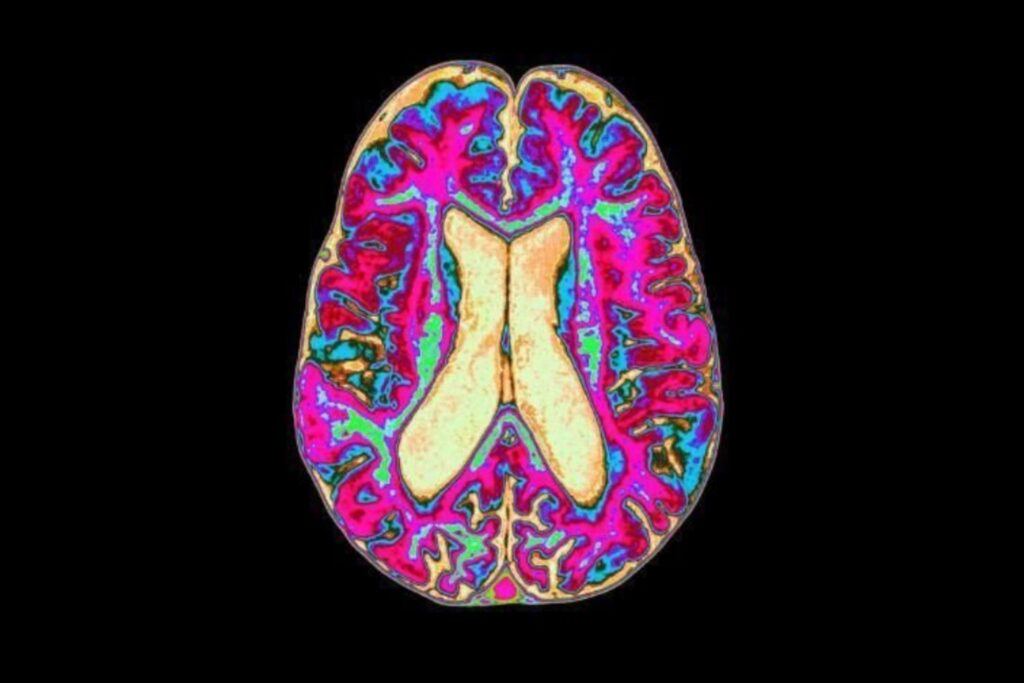

Un estudio de Yale y Cornell revoluciona la visión del metabolismo cerebral al demostrar que las neuronas usan lípidos como combustible.